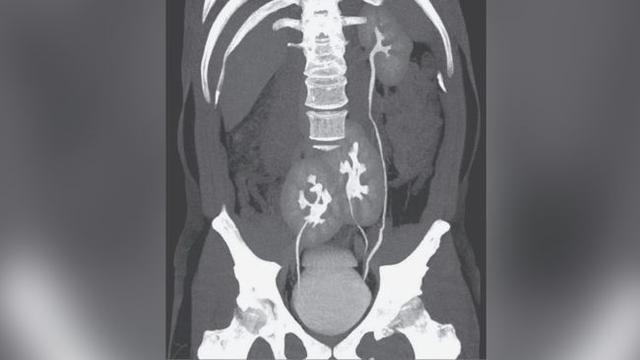

Ảnh chụp CT 3 quả thận.

Trang Aboluowang đưa tin, ngày 6/5, một người đàn ông đến Bệnh viện Do Rim ở Sao Paulo, Brazil phàn nàn về chứng đau thắt lưng. Bác sĩ sốc khi phát hiện ra bệnh nhân có 3 quả thận thay vì là 2, đây là một trường hợp rất hiếm gặp.

Tuy nhiên, người đàn ông này không đơn thuần là bị thoát vị đĩa đệm mà có thêm một quả thận không mong muốn. Bác sĩ cho biết bệnh nhân không có bất kỳ triệu chứng bất thường nào về thận và cơ quan này có vẻ như đang hoạt động tốt.

Thông thường, mỗi quả thận được kết nối với bàng quang thông qua một ống niệu quản. Trong trường hợp của người đàn ông này, một quả thận vùng chậu được kết nối trực tiếp với bàng quang thông qua niệu quản. Tuy nhiên, niệu quản của khung chậu thận khác được kết nối với niệu quản của quả thận trái trước khi vào bàng quang.